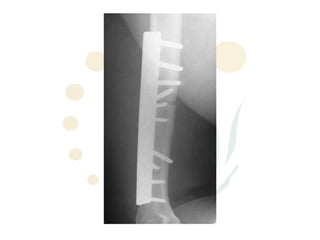

Radial Nerve Palsy

• Causes:

– Fractures esp humerus, Monteggia

– Penetrating injury/trauma

– “Saturday Night Palsy” “Crutches”

– Iatrogenic

– tumour